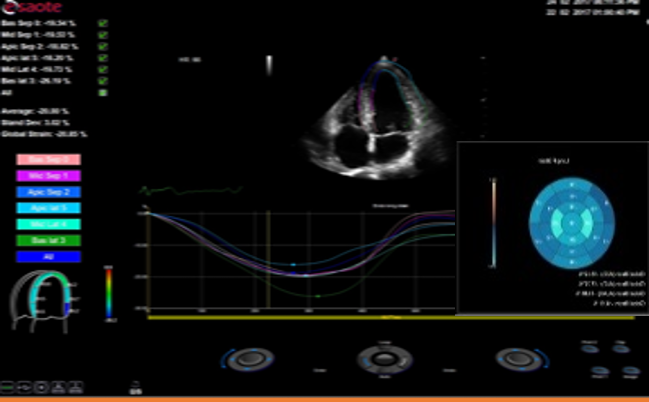

Xstrain – Comprehensive assessment for the myocardial strain of Left Ventricle, a useful tool to evaluate the LV function and Heart diseases

Auto EF – Automatic measurement of the EF fraction